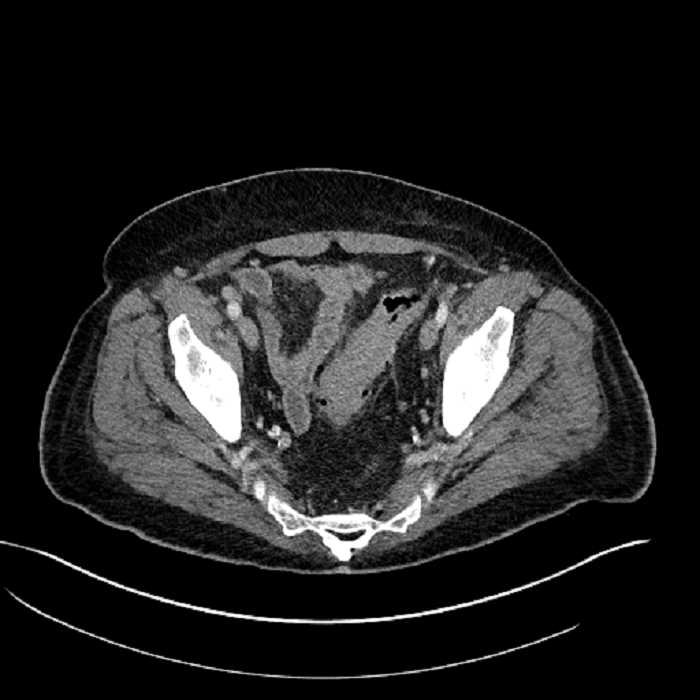

Age: 63

Sex: Male

Indication: Abdominal pain

• High grade stenosis of the left common iliac artery, with the left internal and external iliac arteries remaining patent

• Ankylosis of both sacroiliac joints

Acute sigmoid diverticulitis complicated by a small contained perforation and a large abscess in the right hepatic lobe. Additional small subcapsular abscesses along the anterior margin of the left hepatic lobe.

High grade stenosis of the left common iliac artery. The left external and internal iliac arteries are patent.

Hepatic abscess showing the double target sign with low density internally surrounded by a thin inner enhancing rim (red arrow) and ill-defined outer low density rim (yellow arrow). Blue arrow indicates an internal septation. Red arrows: additional smaller subcapsular abscesses. Red arrow: focal contained perforation associated with diverticulitis.